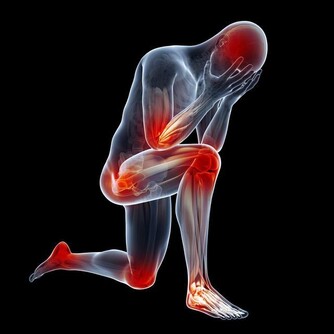

1、延緩骨骼老化

一個人衰老,骨骼會率先顯現脆弱的一面,延緩骨骼衰老對促進年輕很有幫助。相比跑步,太極的活動量並不大,在這輕緩的動作裡,能改善血液循環,對提高骨骼的物質代謝也有幫助,鈣、磷沉澱在骨骼裡,會增強骨骼的密度、彈性,進而可以預防骨質疏鬆的發生,不斷的延緩衰老。